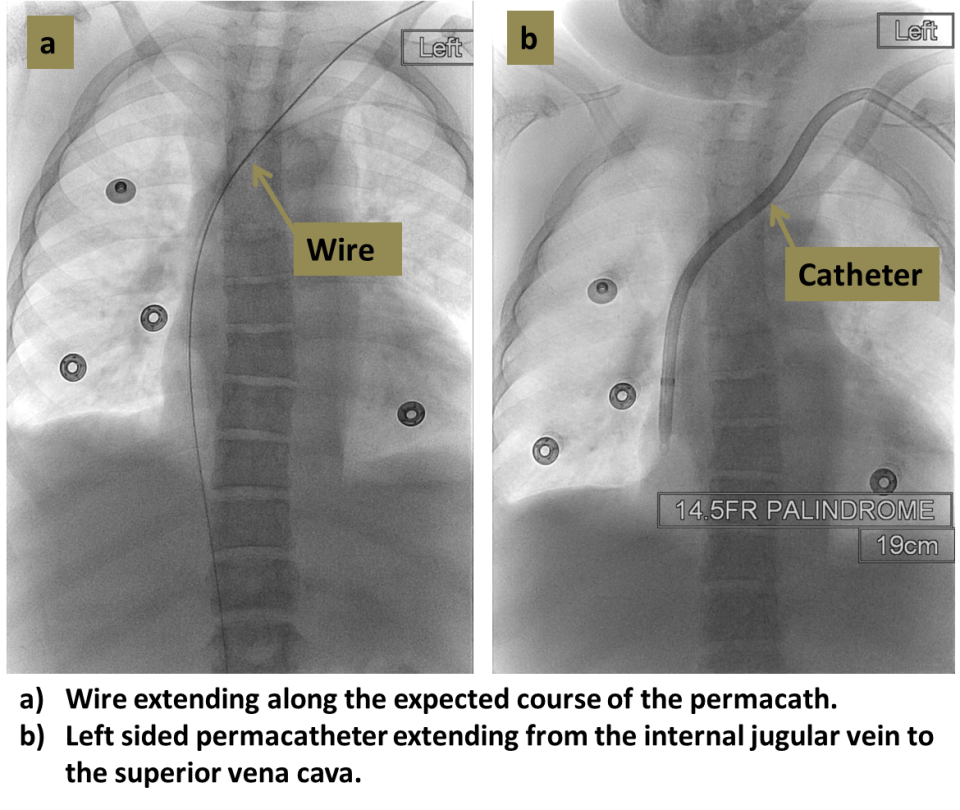

From www.mdpi.com

Diagnostics Free FullText UltrasoundGuided Femoral Vascular Cut Down Vascular Access It is mostly done in cases of emergency where rapid access is required for intravenous (iv) fluid therapy. A prospective study comparing surgical cutdown and percutaneous closure devices for site management of large bore. Learn about different procedures to gain vascular access for iv fluid and drugs, such as peripheral vein, central venous, midline, arterial, and intraosseous catheterization. A cutdown. Cut Down Vascular Access.